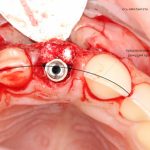

Рекомендации по установке имплантов. Для всех. Часть V.